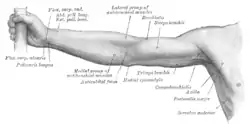

Still image. Lateral view. Front of right upper extremity. (Coracobrachialis labeled at right, fourth from the bottom.)